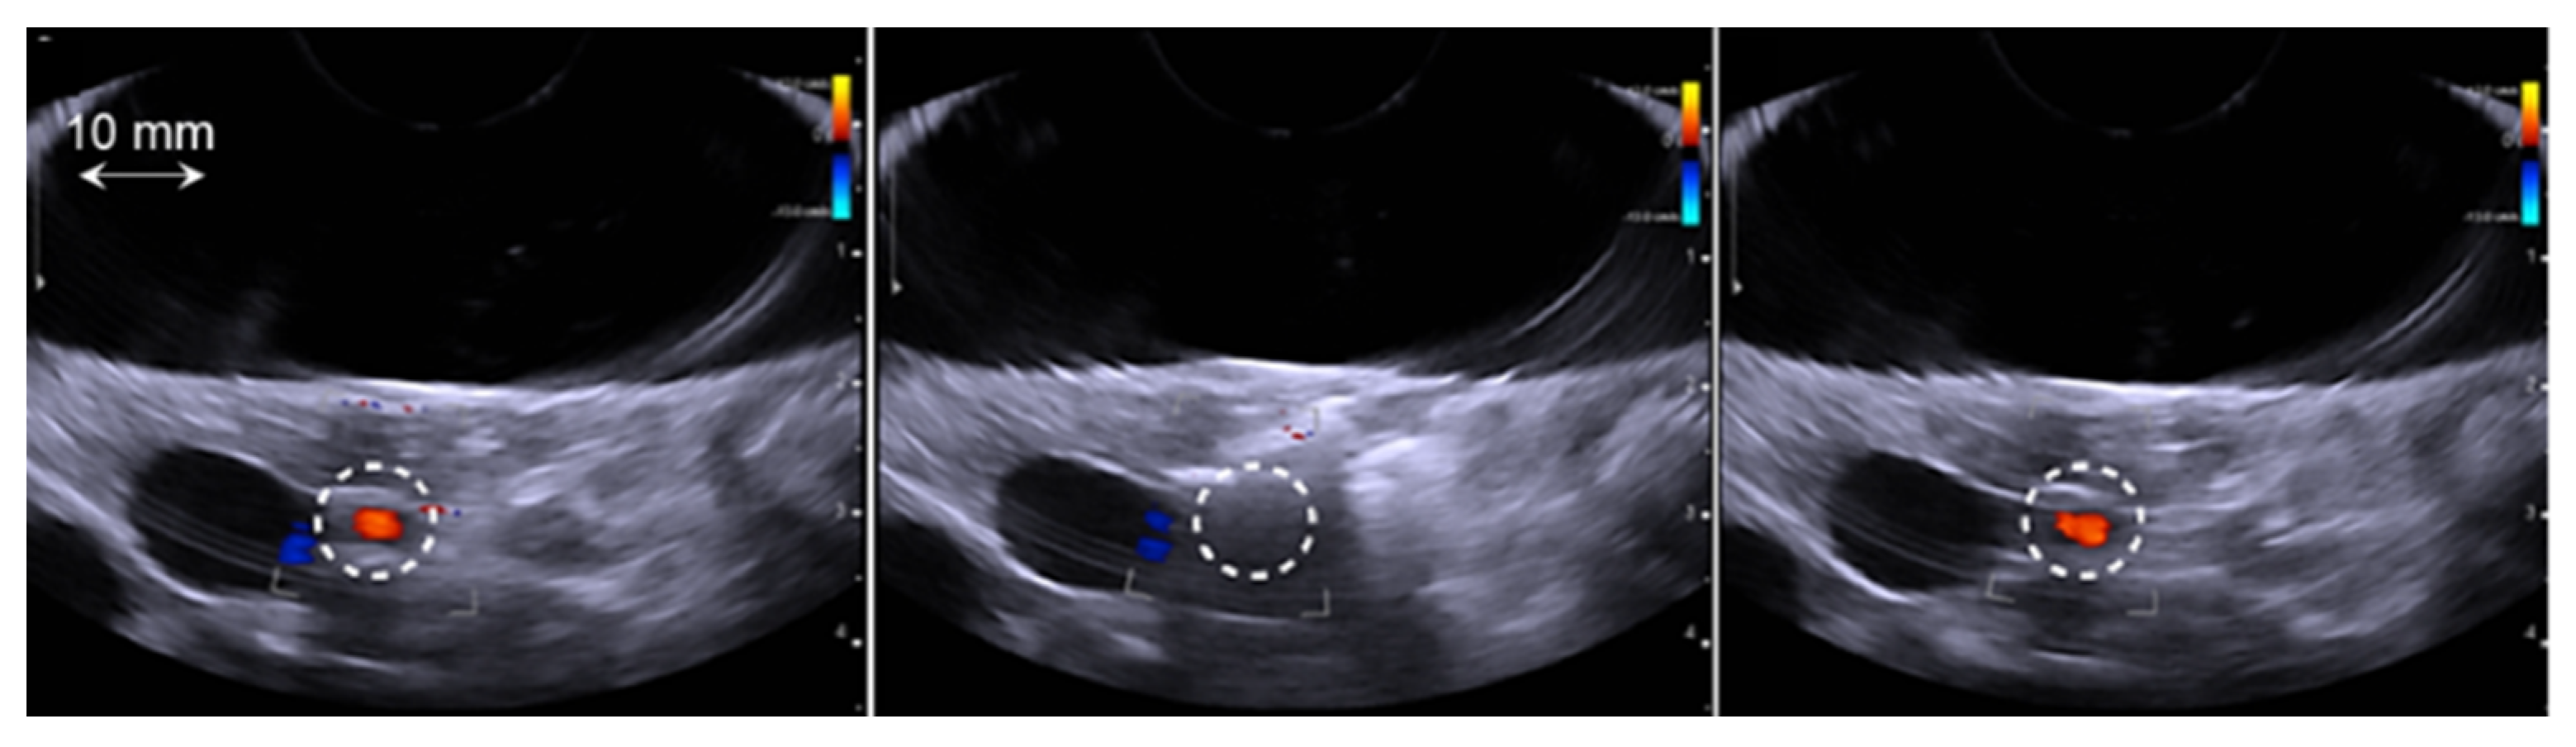

3.3. Analysis of HIFU Treatment